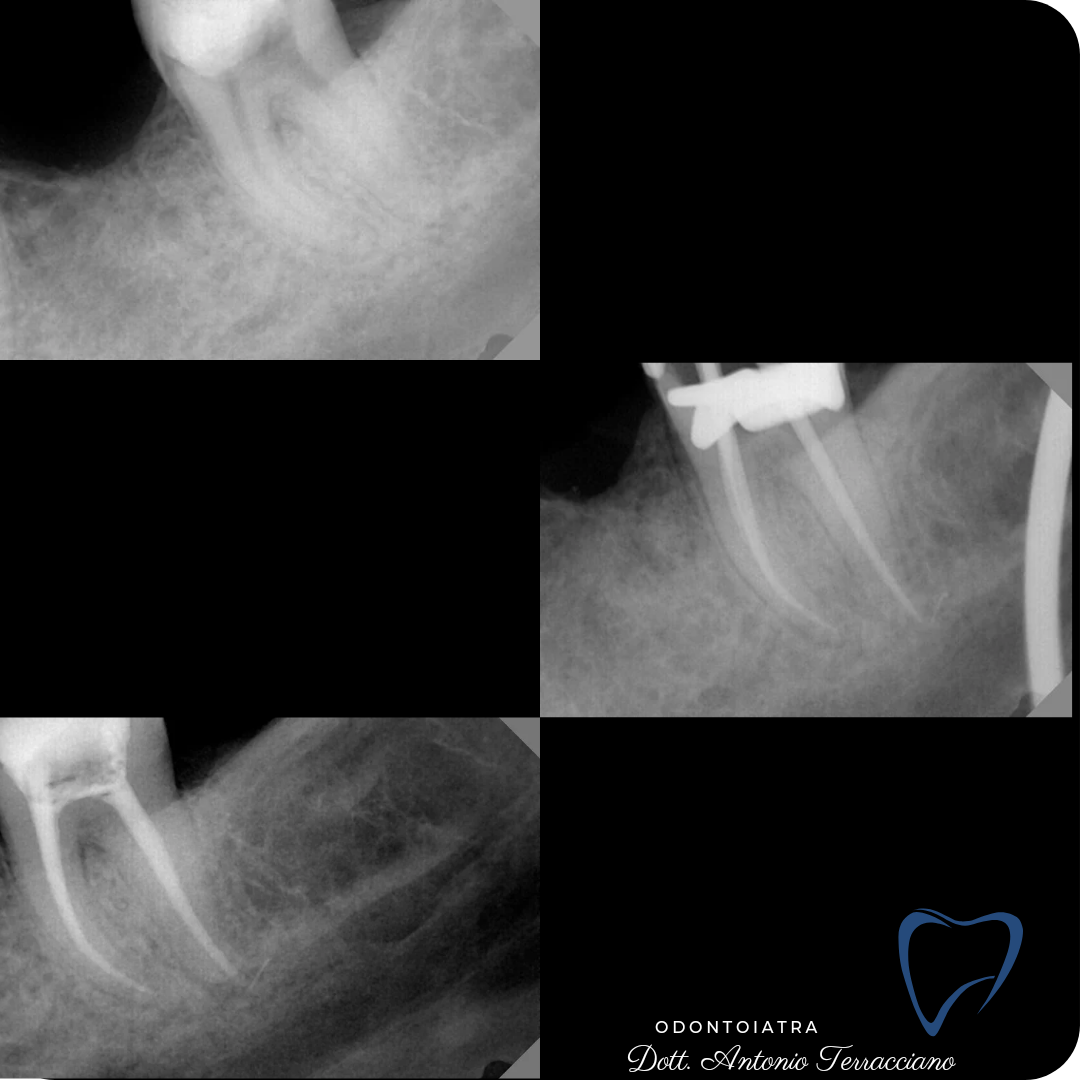

RITRATTAMENTO

Ritrattamento di un premolare, con protaper gold fino a conicità 20.06, si attiva NaOCl 5,75% con tecnica System B e si chiudono i canali con bioceramico e cono master